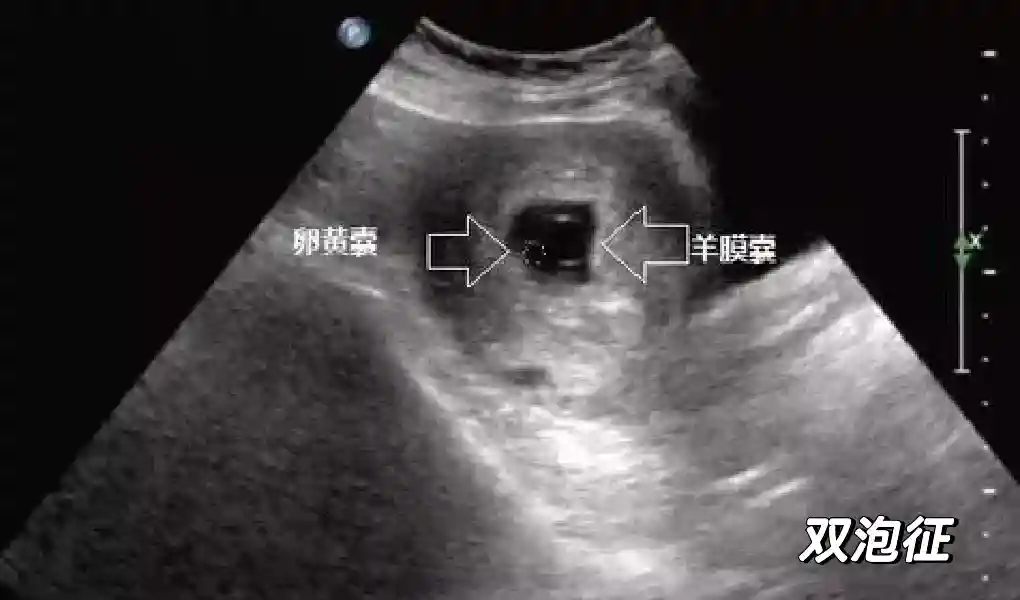

2??卵黄囊:是妊娠囊内第一个解剖结构,直径<7mm。表现为小环状,中央为无回声,囊壁薄,内透声好。卵黄囊位于胚胎旁胚外体腔内。卵黄囊通常在孕5-6周时出现,5-10周稳步增长,一般不超过7mm,至12周消失。妊娠囊的大小与卵黄囊之间有一定关系,妊娠囊平均直径> 8 mm 时,经阴道超声均应显示卵黄囊,妊娠囊平均直径> 18 mm 时,经腹超声均应显示卵黄囊。

5??羊膜:早孕期羊膜囊菲薄,超声常不能显示。孕7周以后加大增益或者用高频超声可以显示羊膜。羊膜囊位于绒毛膜内,胚胎位于羊膜囊内。随着胚胎增长,羊水增多,羊膜囊增大,孕12-16周时,羊膜与绒毛膜全部融合,胚外体腔消失。宫腔线一侧内膜内一圆形增强回声区,中央有小囊状液性暗区,宫腔线局部突起变形,称蜕膜内征,用于判断早早孕。